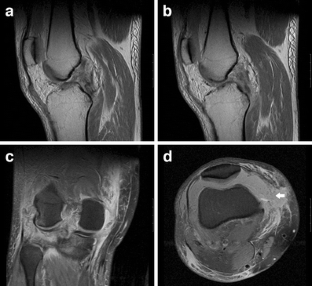

Fig. 2